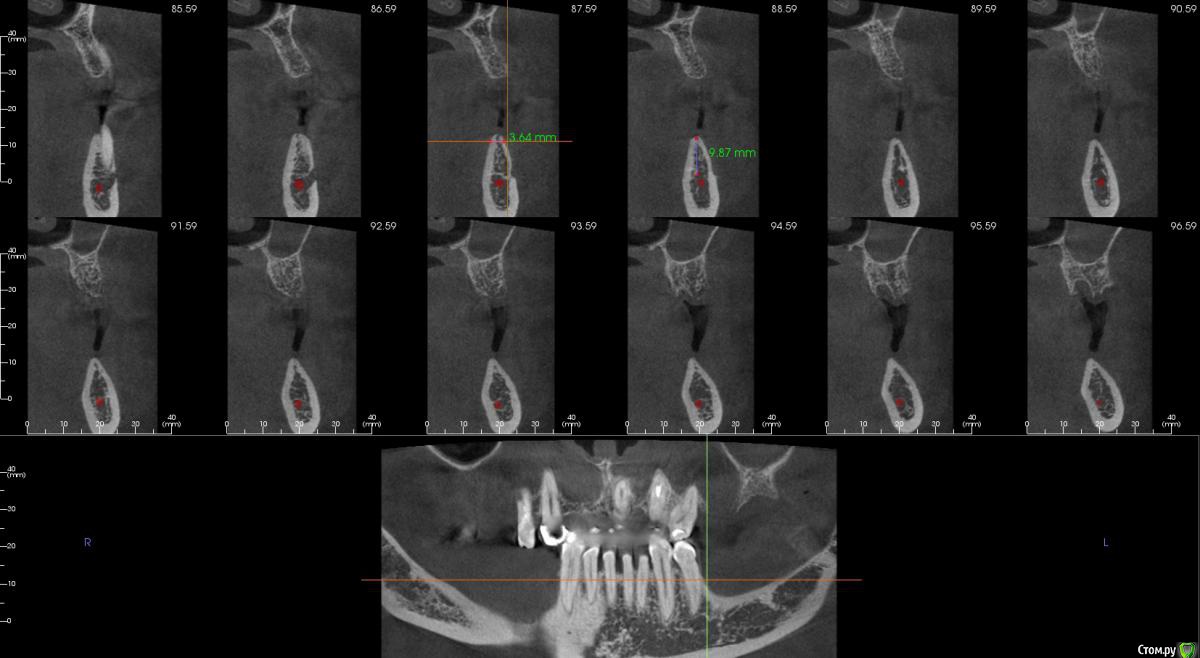

kamranchick Опубликовано 17 февраля, 2015 Поделиться Опубликовано 17 февраля, 2015 Добрый вечер.Имеется следующая проблемаПациент обратлся с жалобами в области отсутствия жевательных зубов, планируется имплантация.Вопросы такого плана, в области 3 сегмента думаю сделать расщепление гребня, установка имплантов 3,75/8 и аугментация костью Ostebiol Gen-Os, мембрана.В области 4 сегмента больше сомнения, планируется титановая сетка +аугментация, либо расщепление опять же, планирую разделить восстановление и имплантауию на 2 этапа в 4 сегментеКакие будут комментарии? Ссылка на комментарий